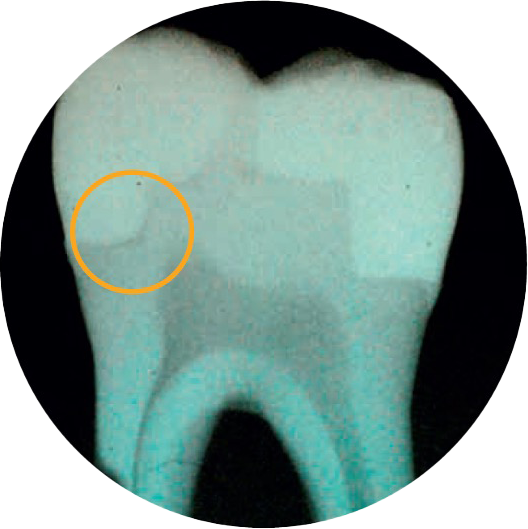

Imagen:

Antes: restauración posterior con composite restaurador Spectra ST de color A2 (Fuente: Dr. A. Ferrando)

Después: sustitución de amalgama con una técnica de estratificación avanzada, utilizando el color A2 y Bleach White del composite restaurador Spectra ST